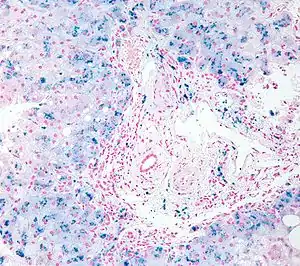

| Micrograph of a liver biopsy showing iron deposits due to iron overload. Iron stain. | |

Liver biopsy is the removal of small sample in order to be studied and can determine the cause of inflammation or cirrhosis. In someone with negative HFE gene testing, elevated iron status for no other obvious reason, and family history of liver disease, additional evaluation of liver iron concentration is indicated. In this case, diagnosis of haemochromatosis is based on biochemical analysis and histologic examination of a liver biopsy. Assessment of the hepatic iron index (HII) is considered the "gold standard" for diagnosis of haemochromatosis.